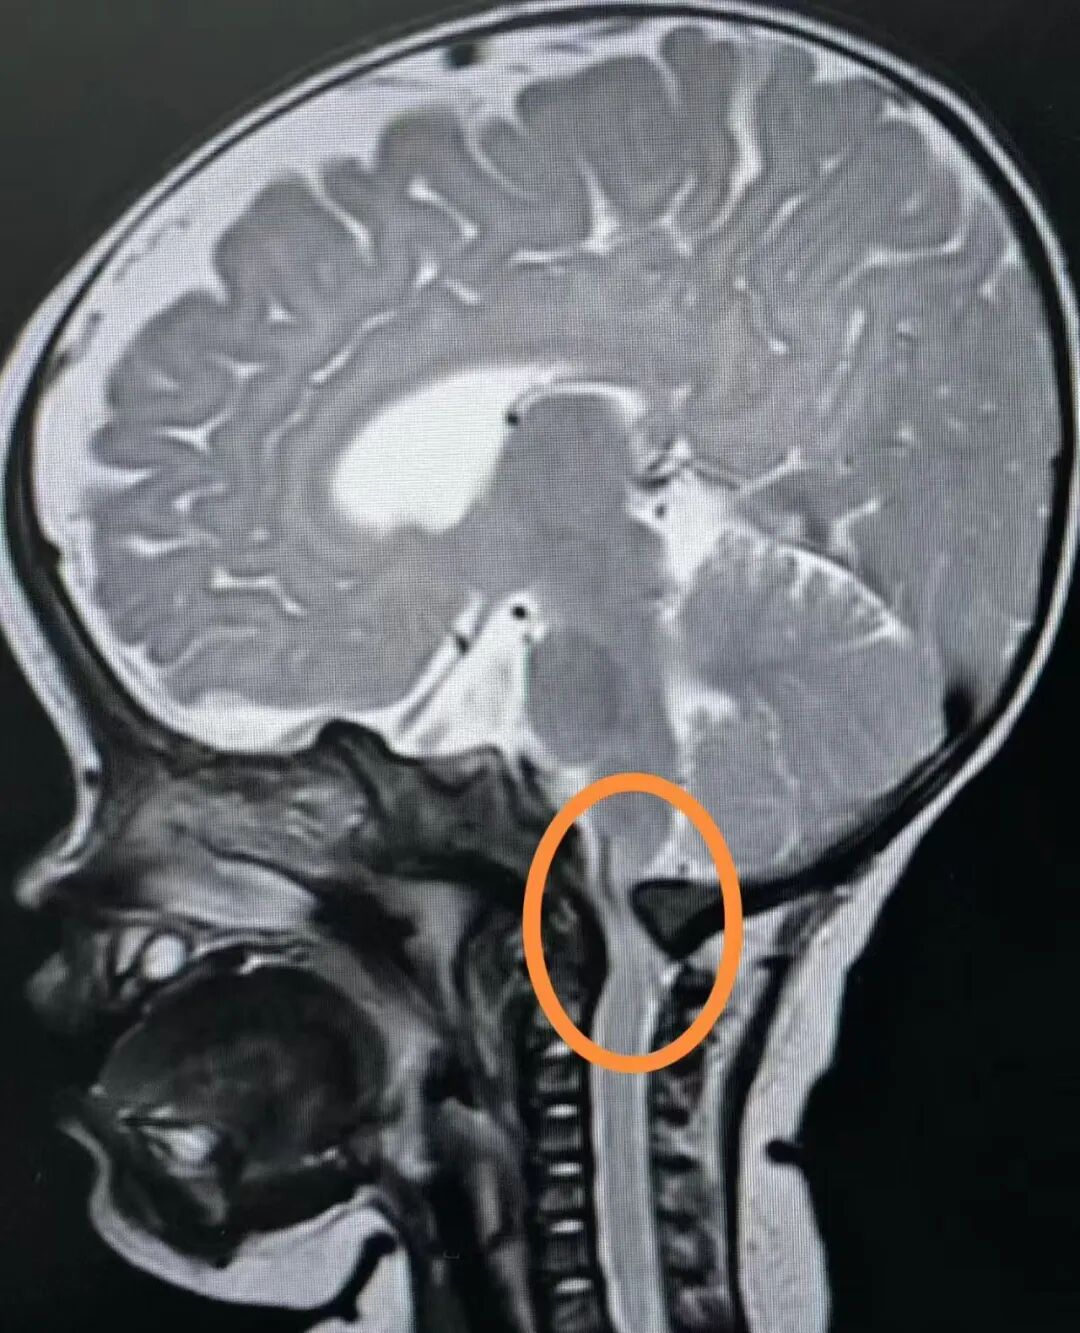

宝宝术前的磁共振,显示IV级压迫,脊髓有变性(张晨冉主任提供)

所以我们也是在那边出院了不久,马上和家人带着孩子来上海这边来就医,希望能赶紧把这个手术做掉。因为我们也属于不幸中的万幸吧,也是因为这个意外才发现了这个问题。而且一发现就是四级,需要尽快手术的这种。